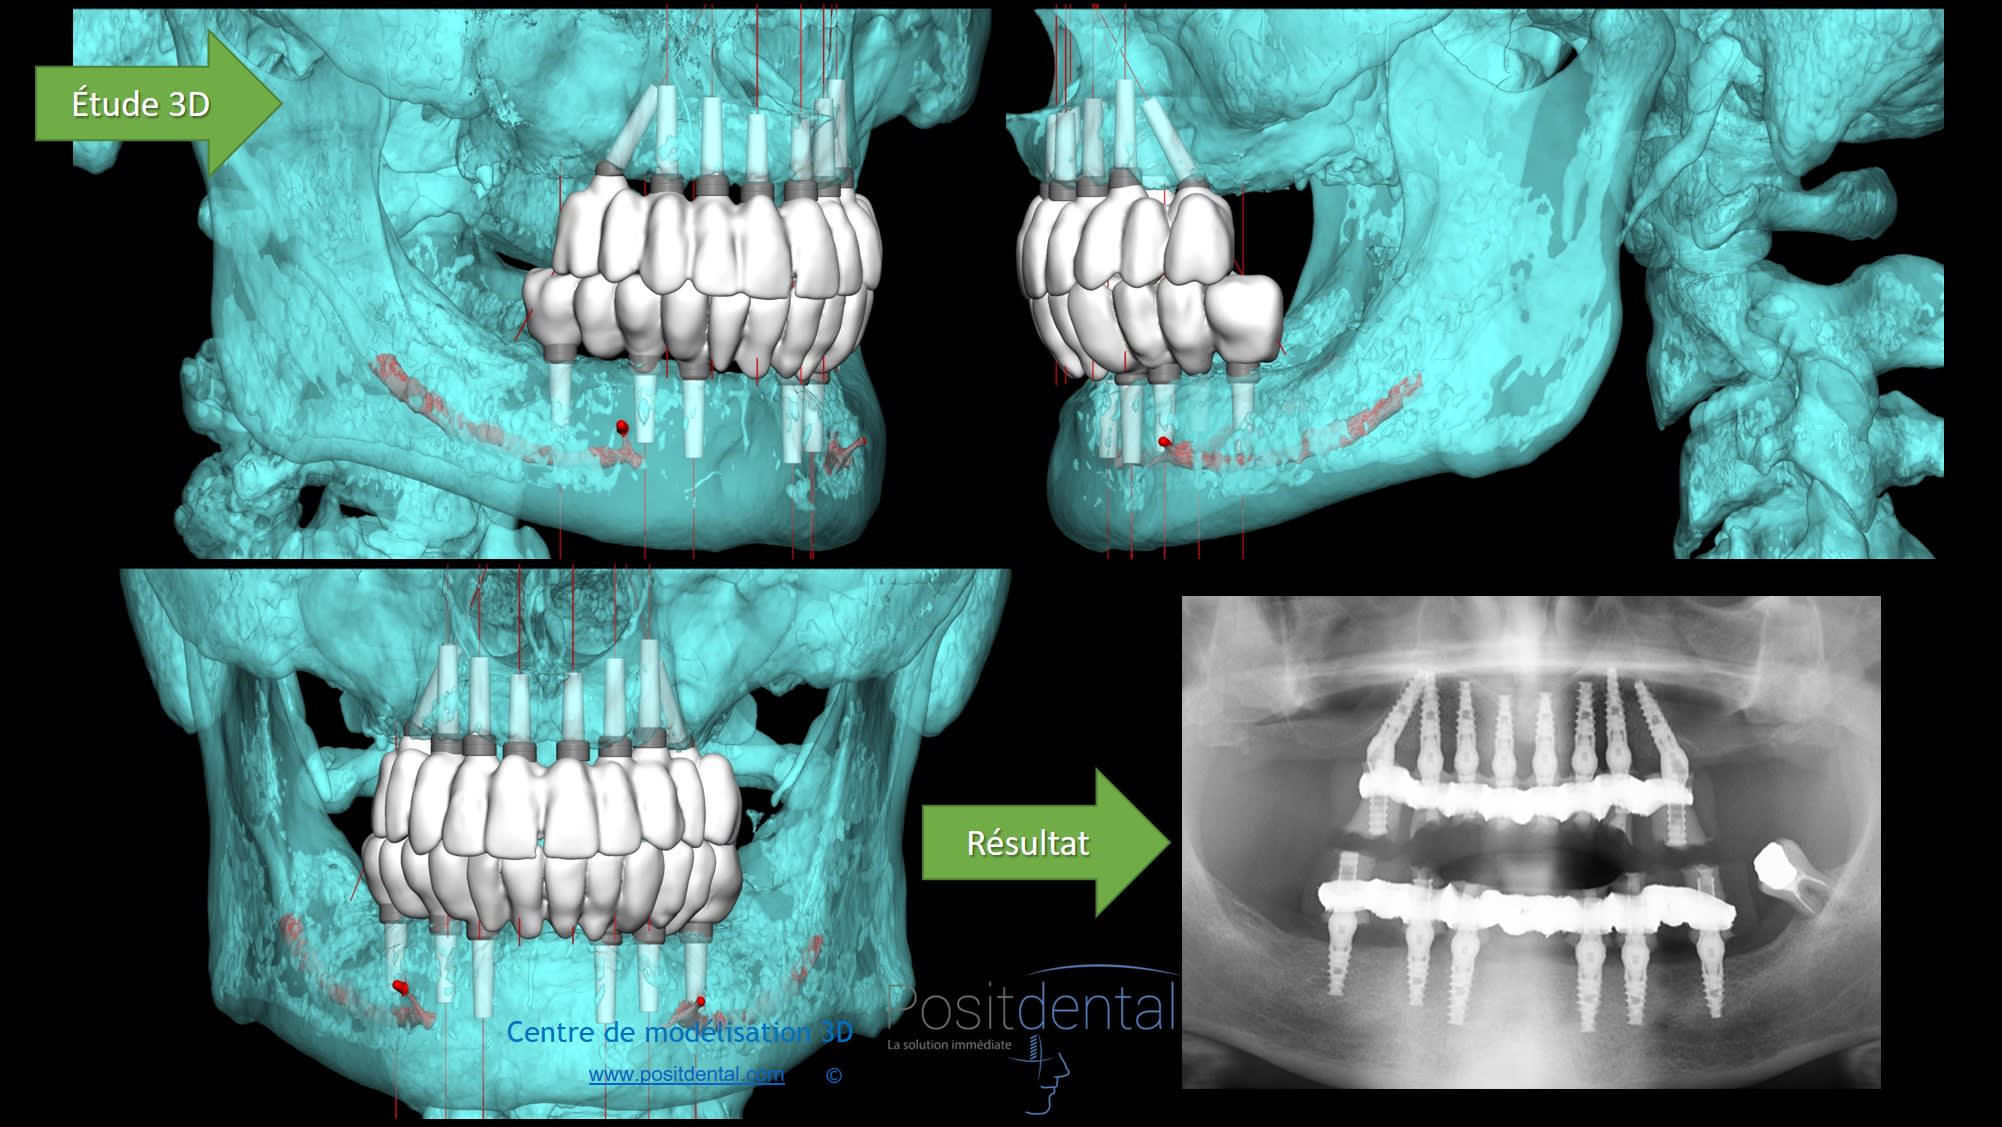

Les indications clinique ce n'est pas moi qui les poses par contre la simulation implantaire et les DMSM avec toute les justificatifs et données technique pour qu'une fois validées le praticien puisse réalisé ça oui

Modélisation 3d et résultat clinique hdgupg - Eugenol

Mais pourquoi avoir gardé cette pauvre molaire mandibulaire ???... C était pour être sûr d avoir assez de biofilm pour contaminer les sites ??

T as la pano du patient avant son edentation ?

Tu as du lire dans des études scientifique que même des années post extraction chez l'édenté total les bactéries responsables des parodonties sont présentes.

Merci de tes conseils et pour ce cas tu as un avis ?

Modélisation 3d et résultat clinique ygsom6 - Eugenol

Oui et c'est pour cela que je te parle bien de biofilm... les mots on un sens.

tres honnêtement, la conservation de cette molaire questionne... pourquoi l'avoir gardée ? quelle est son rôle ?